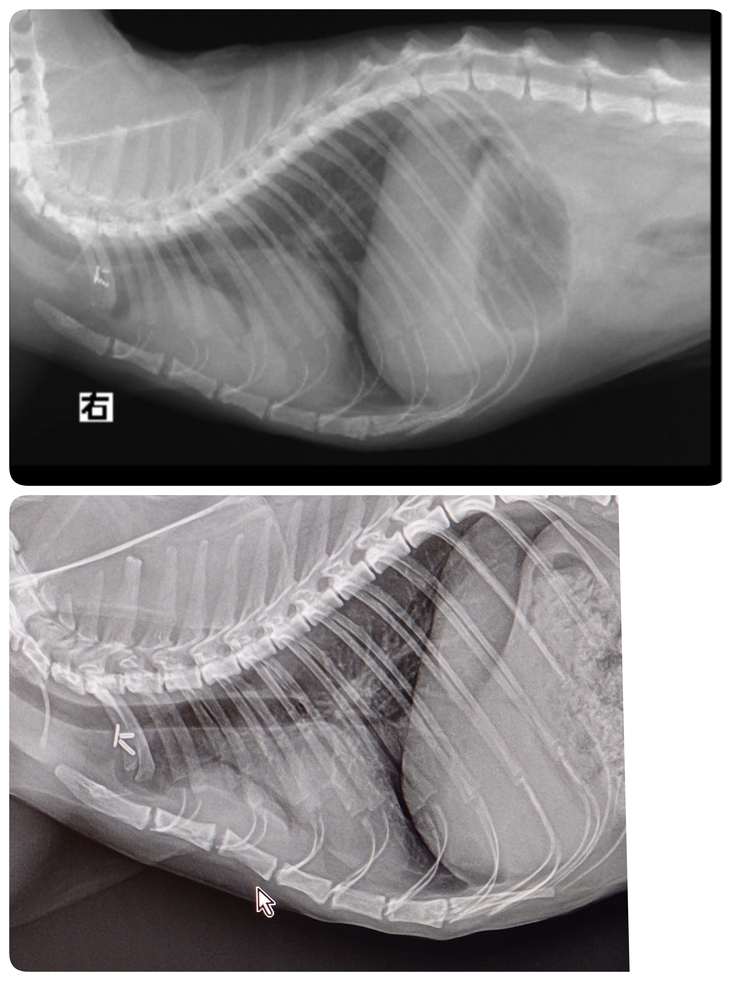

さらに、その時に撮影したレントゲンで胸腺腫の再発が見つかってしまったんです

3✕5cmまで大きくなっていました